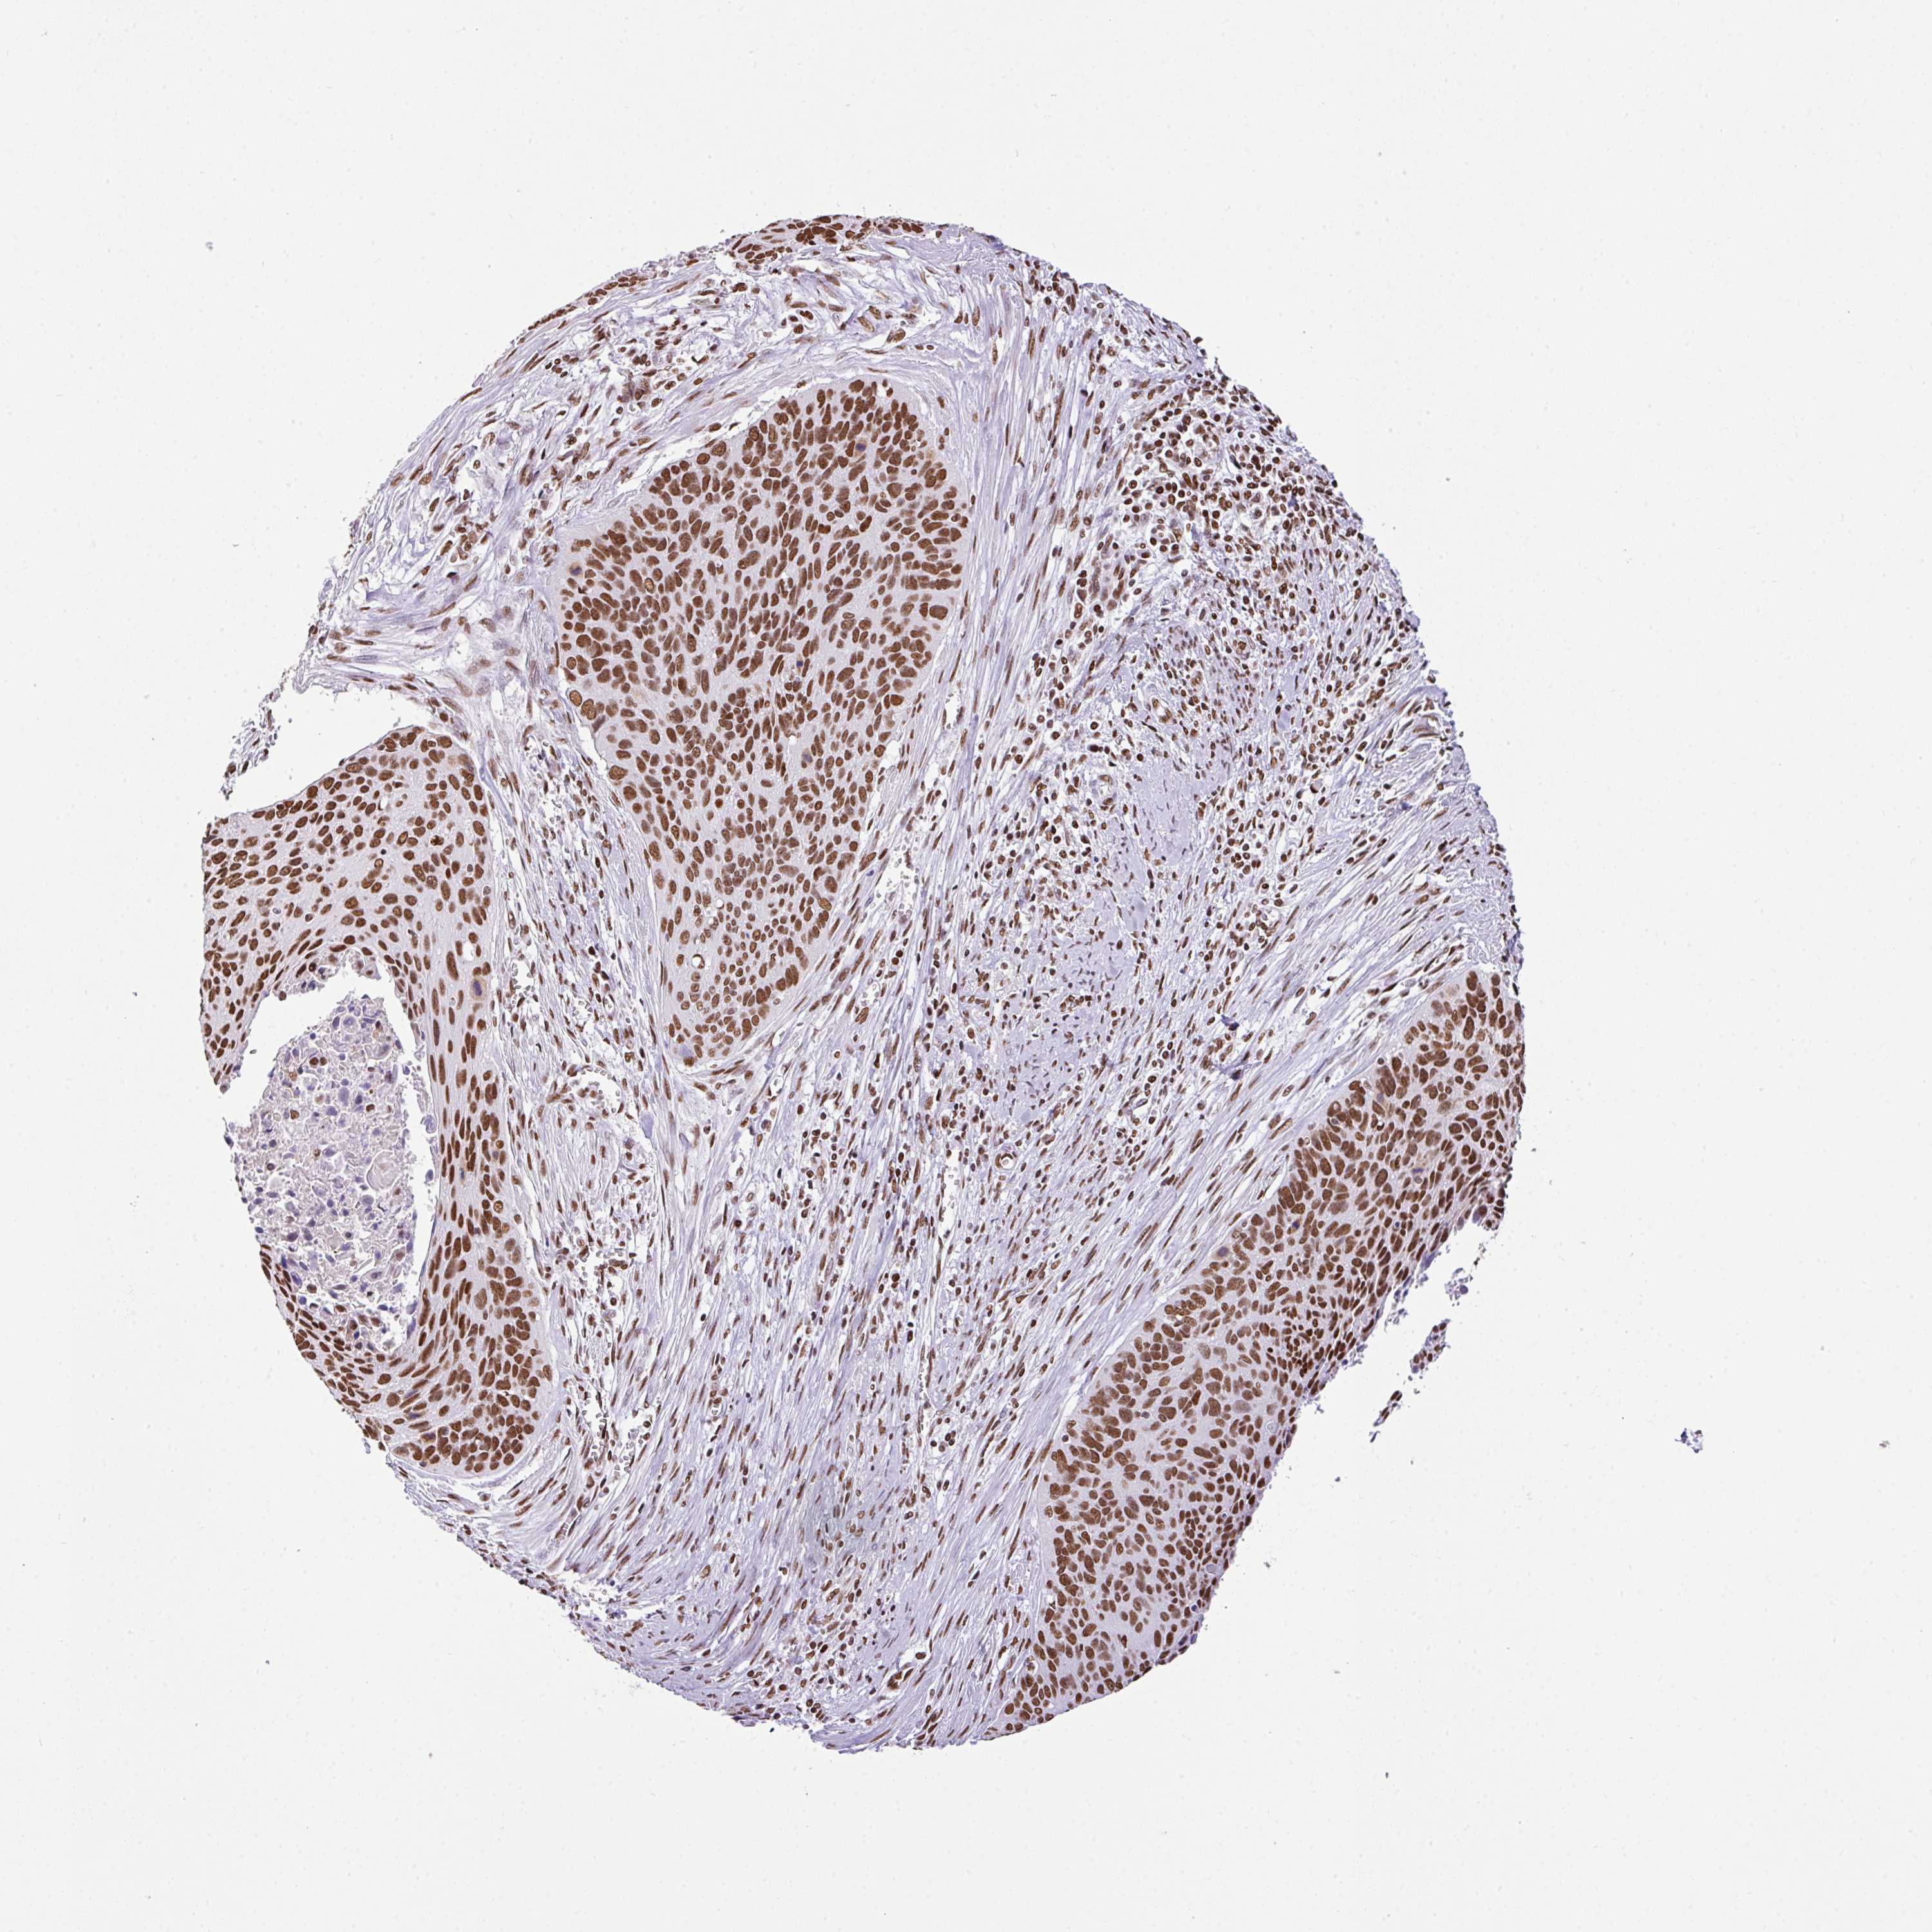

CERVICAL CANCER - Protein expressioni

A mouse-over function shows sample information and annotation data. Click on an image to view it in a full screen mode. Samples can be filtered based on level of antibody staining by selecting one or several of the following categories: high, medium, low and not detected. The assay and annotation is described here.

Note that samples used for immunohistochemistry by the Human Protein Atlas do not correspond to samples in the TCGA dataset.

Antibody stainingi

Antibody staining in the annotated cell types in the current human tissue is reported as not detected, low, medium, or high, based on conventional immunohistochemistry profiling in selected tissues. This score is based on the combination of the staining intensity and fraction of stained cells.

Each image is clickable and will lead to virtual microscopy that enables deeper exploration of all samples and also displays staining intensity scores, fraction scores and subcellular localization as well as patient and tissue information for each sample.

Antibody HPA053883

Staining

High

Medium

Low

Not detected

Intensity

Strong

Moderate

Weak

Negative

Quantity

>75%

75%-25%

<25%

None

Location

Nuclear

Cytoplasmic/membranous

Cytoplasmic/membranous,nuclear

Adenocarcinoma, NOS